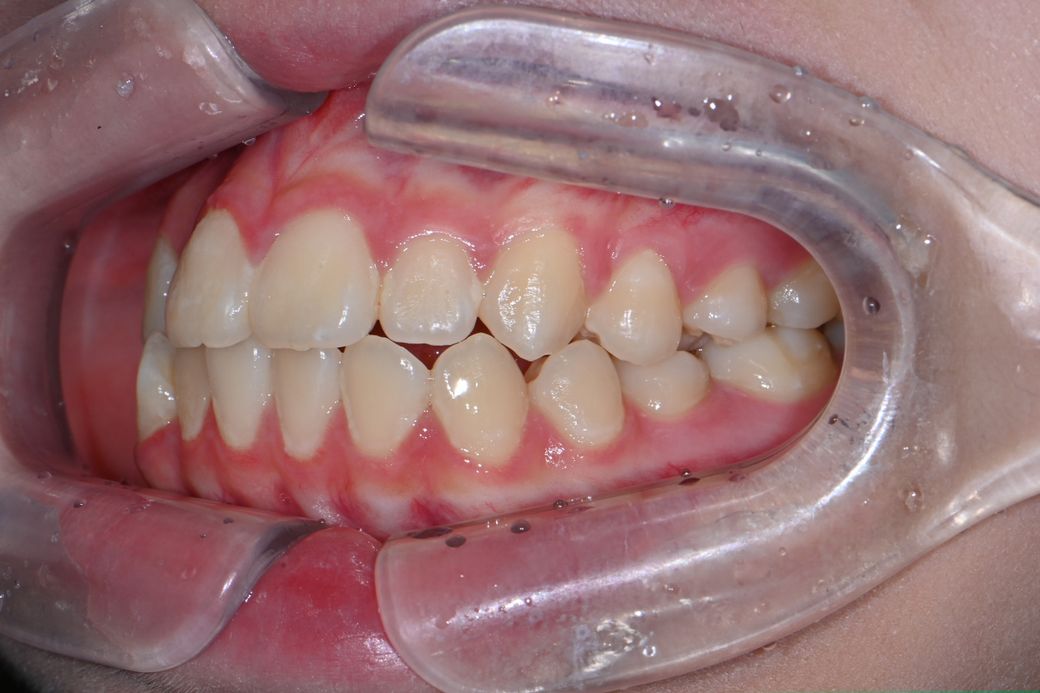

중1 여자 아이 교정진단 부탁드립니다.

앵글씨 몇급인지 궁금합니다.

의사 선생님마다 소견이 다르셔서 혼란 스럽네요.중1 여자 아이구요.시기적으로 지금 교정을 시작하기에 적절한지 궁금합니다.

• 3번 째 사진

앵글 2급 부정교합이며, 지금 교정하는 것이 좋을 것으로 보입니다. 더 늦어지면 교정이 까다로워 질 수도 있습니다. 지금 현재도 쉬운 케이스는 아닙니다.

앵글씨 부정교합측면에서 보면 1급인거 같고 치열이 좋지 않아서 중학교 1학년이면 교정을 시작하셔도 괜찮을 시기인거 같습니다.